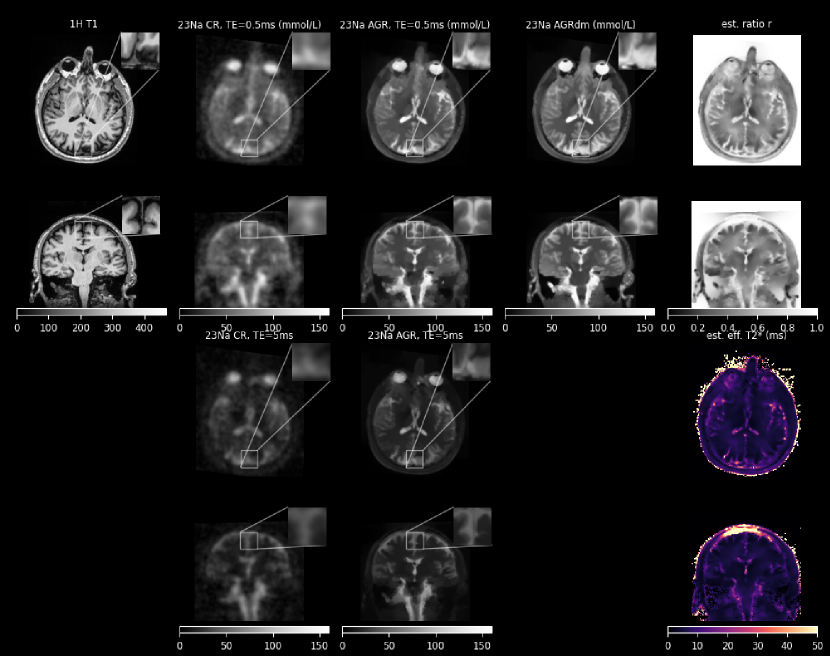

Figures 5, 6, and 7 show the conventional (CR) and anatomically-guided sodium reconstruction without and with signal decay estimation and modeling (AGR and AGRdm) for the three dual echo sodium acquisitions. In all three cases, the boundaries between GM, WM and CSF are much better defined in the anatomically-guided reconstructions, leading, e.g., to a clearer separation between the sodium concentration in GM and WM and also between the CSF in the sulci and cortical gray matter. Moreover, within WM and GM, both AGRs are less noisy compared to the conventional reconstruction. The estimated decay ratio image (the exponential transformation of the effective estimated monoexponential T2superscriptsubscript𝑇2T_{2}^{*} time) clearly shows the relatively slow signal decay in CSF (r𝑟r close to 1) and faster decay in GM and WM. Figure 8 shows a comparison of the sodium concentration of GM and WM in the cortical region obtained with the three reconstructions in all three cases. The higher cortical GM to WM contrast of AGRdm that can be also clearly seen in Fig. 5 is also confirmed in the plot of cortical GM to WM sodium concentration displayed in the right of Fig. 8. Morever, AGR and AGRdm also lead to higher GM to brainstem sodium concentration ratios which are more in line with the ratios of healthy controls reported in [7] where partial volume correction was applied post reconstruction in image space.

Figure 5: Dual echo sodium reconstructions of a healthy control (60yr, M) acquired on a 3T Siemens Prisma. (top left): 1H T1 used as anatomical prior. (top 2nd from left): conventional reconstruction (CR) of the first echo (top middle): anatomically-guided reconstruction of the first echo without signal decay modeling (AGR) (top 2nd from right): anatomically-guided reconstruction of both echos including signal decay estimation and modeling (AGRdm). (top right): estimated ratio between the first and second echo (r𝑟r) used for the monoexponential signal decay modeling. (bottom 2nd from left): conventional reconstruction (CR) of the second echo (bottom middle): anatomically-guided reconstruction of the second echo without signal decay modeling (AGR) (bottom right): effective estimated monoexponential T2superscriptsubscript𝑇2T_{2}^{*} time calculated from r𝑟r. The signal intensity of all sodium images (including the 2nd echo images of CR and AGR) is normalized to the mean signal intensity of AGRdm in vitreous humor (145 mmol/L) and shown using the same color scale. Due to the impact of the T2superscriptsubscript𝑇2T_{2}^{*} decay, the units of the second echo images are not labeled as mmol/L.

Figure 6: Same as Fig. 5 for the second healthy control (65yr, F).